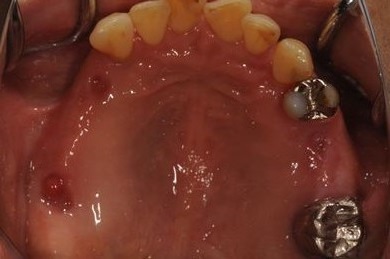

| 性別/年齢 | 女性 / 51歳 | ||||||||||||||||||||||||||||||||

| 主訴 | 他の歯科医院で入れ歯を入れたが、滑舌や味などで不自由を感じている。インプラントは難しいと言われたが、可能かどうかみていただきたい。 | ||||||||||||||||||||||||||||||||

| 治療方針 | サイナスリフトにより上顎洞を拳上し、インプラント治療を可能にする。 | ||||||||||||||||||||||||||||||||

| 治療内容 | インプラント3本(サイナスリフト)、ハイブリッドセラミッククラウン5本 | ||||||||||||||||||||||||||||||||